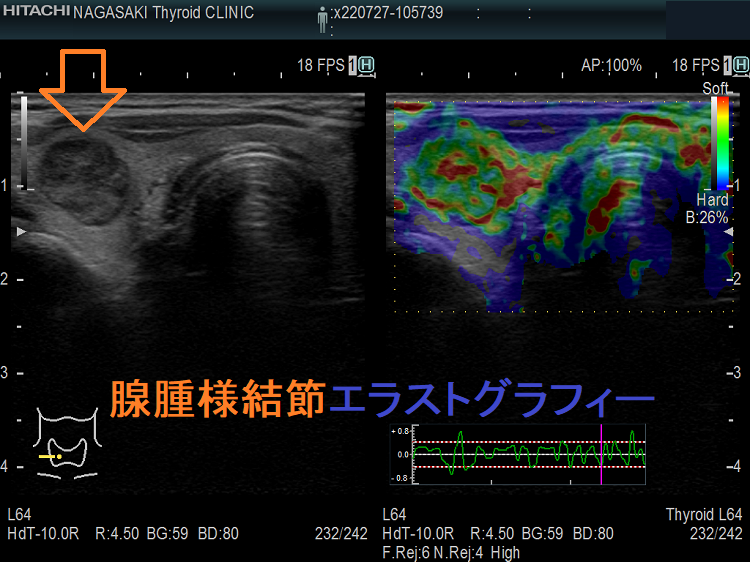

甲状腺良性濾胞腺腫腺腫様結節エラストグラフィー

エラストグラフィー (甲状腺良性濾胞腺腫)

甲状腺良性濾胞腺腫エラストグラフィー(JTEC パターン1)。甲状腺良性濾胞腺腫は、軟らかいために見えます。

腺腫様結節 エラストグラフィー

腺腫様結節エラストグラフィー(JTEC パターン1)。腺腫様結節は、軟らかいために見えます。